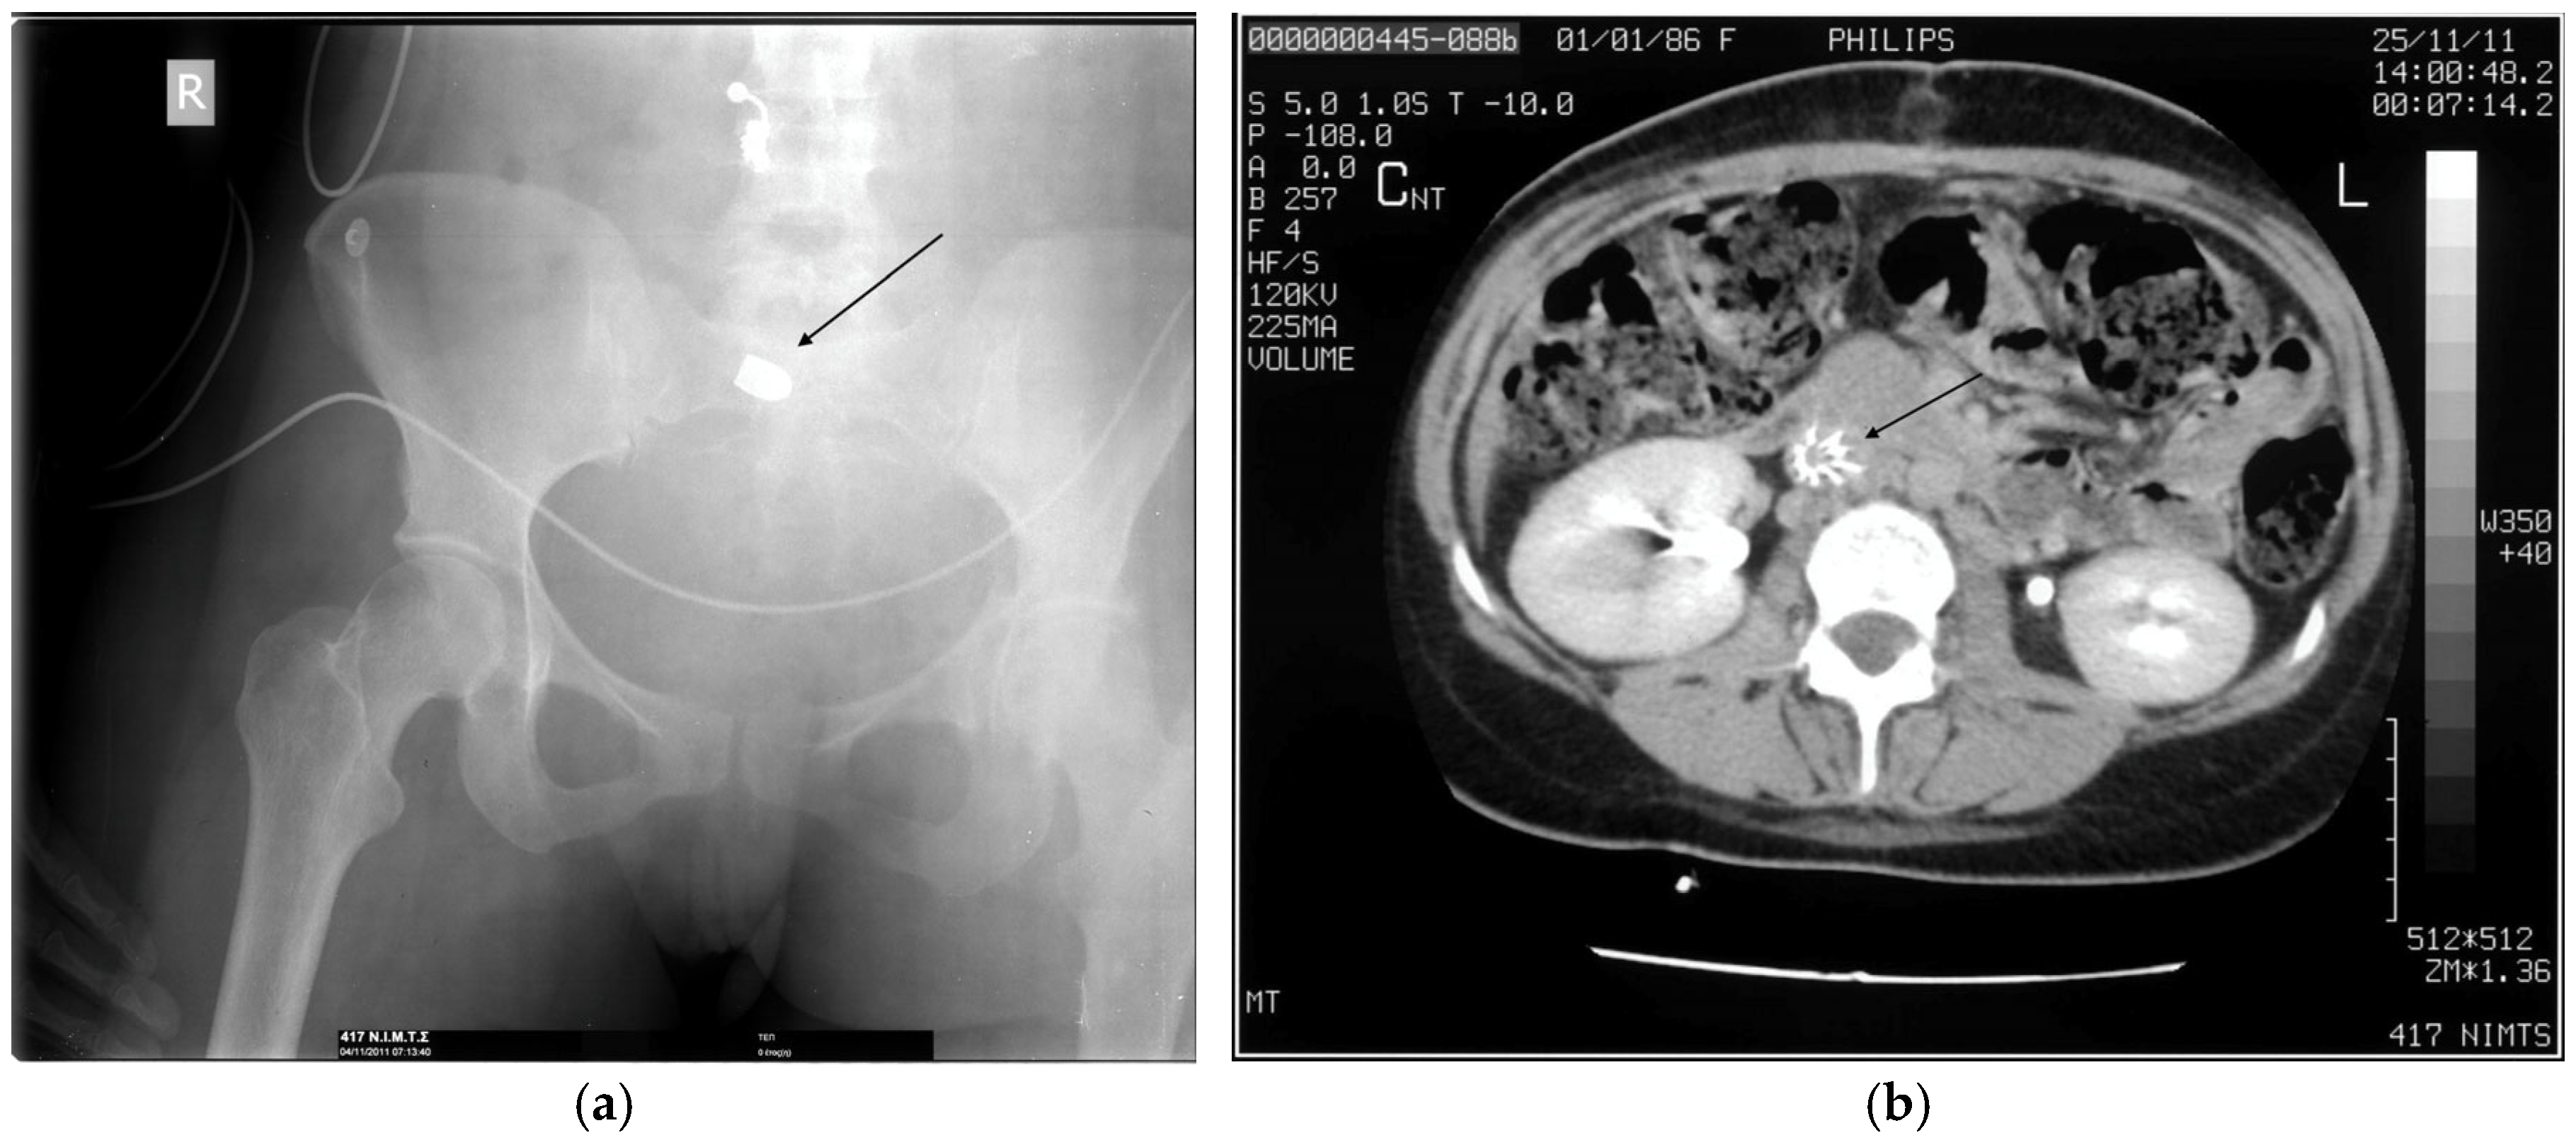

- Reginelli, A.; Russo, A.; Maresca, D.; Martiniello, C.; Cappabianca, S.; Brunese, L. Imaging assessment of gunshot wounds. Semin. Ultrasound CT MR 2015, 36, 57–67. [Google Scholar] [CrossRef]

- Karademir, K.; Gunhan, M.; Can, C. Effects of blast injury on kidneys in abdominal gunshot wounds. Urology 2006, 68, 1160–1163. [Google Scholar] [CrossRef]

- Serafetinides, E.S. Renal and ureteric trauma. In Primer on Urology; Chapple, C.R., Wein, A.J., Eds.; Springer: Cham, Switzerland, 2025; pp. 1013–1024. [Google Scholar] [CrossRef]